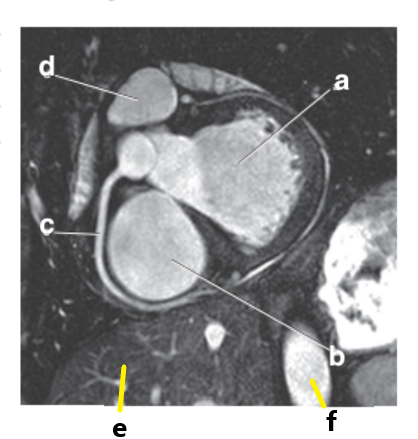

What is letter b ?

Left ventricle

Which letter is the superior vena cava ?

d

What is letter a ?

Left atrium

Right ventricle

What is letter d ?

Which letter is the Right coronary artery ?

c

What is letter g ?

Right atrium

What is letter c ?

Pulmonary trunk

Bicuspid valve / LT AV valve